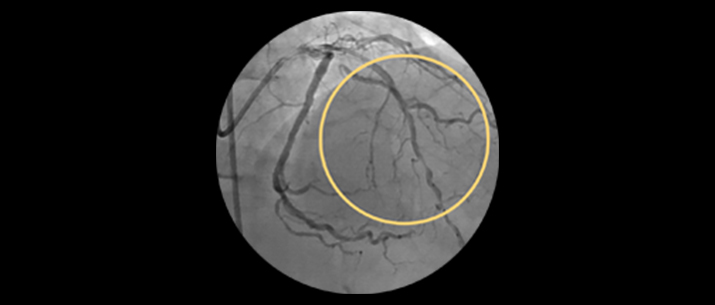

Approximately 20% of the coronary lesions treated today are long and diffuse.1,2

– Stent length is an independent predictor of in-stent restenosis and thrombosis.

– Stenting long segments with multiple and or overlapping stents may lead to injury to the vessel wall integrity.

– Diffuse CAD may be underestimated by evaluation with coronary angiography.

– Determining reference vessel sizing can be challenging when the vessel is diffusely diseased.